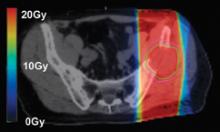

Radiation therapy is an important clinical option for the alleviation of pain and suffering for cancer patients and is used for palliative treatments to prevent pathologic bone fractures or tumor-induced obstructions, bleeding and pain that is resistant to other treatments.

However, standard palliative radiation therapy treatment techniques often offer poor conformality and expose large volumes of normal tissues to radiation-induced toxicities, causing significant side effects for an already ill patient with a limited life expectancy.

Treatment planning is a critical component of a patient’s road toward an optimal outcome when dealing with cancer. Whether the ultimate goal is palliative or a total cure, treatment planning always aims to provide just enough dose to a targeted area to eradicate the cancer, while sparing nearby tissue or organs.